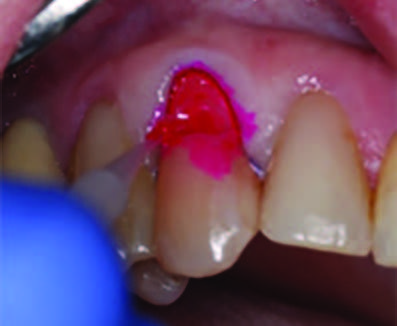

Figure 2. Placement of the retraction cord to improve isolation and access to the cervical area prior to preparation.

Figure 3. Application of caries indicator dye to identify the remaining infected tissue beneath the dislodged composite.